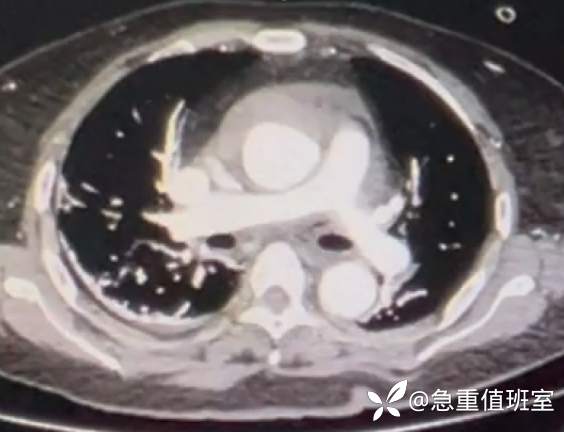

- 主动脉 CTA:急性主动脉夹层 A 型。

图 3 主动脉 CTA